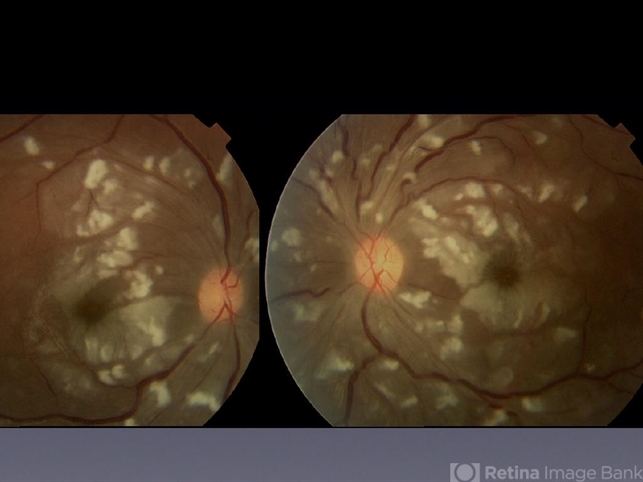

- SLE Retinal Vasculopathy with Retinal Vasculitis and Ischemia

- lupus, systemic lupus erythematosus (SLE) vasculitis, systemic lupus erythematosus (SLE) retinopathy

- Purtscher's-like retinopathy.